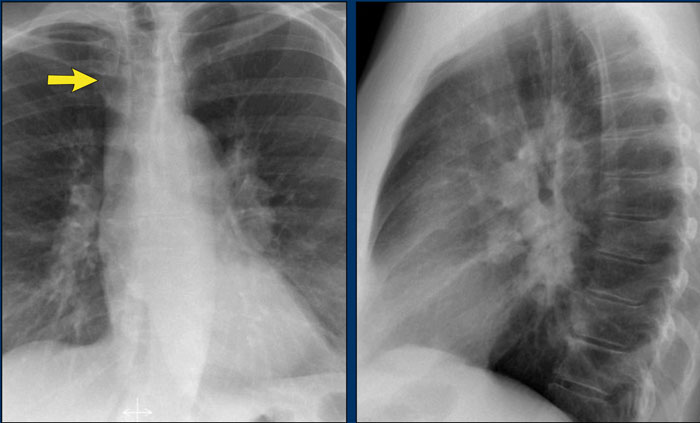

A key mediastinal–pulmonary interface to assess is the azygoesophageal recess (yellow arrow).

Azygo-esophageal recess

The azygoesophageal recess is located below the level of the azygos vein arch.

In this region, the medial aspect of the right lower lobe abuts the mediastinum between the heart anteriorly and the vertebral column posteriorly.

On its left, it is bordered by the esophagus.

Deviation of the azygoesophageal line may result from:

• Hiatal hernia

• Esophageal pathology

• Left atrial enlargement

• Subcarinal lymphadenopathy

• Bronchogenic cyst

On the PA chest radiograph, a lateral displacement of the azygoesophageal line can be seen.

It is caused by a hiatal hernia.

The arrow points to the barium contrast within the hiatal hernia.